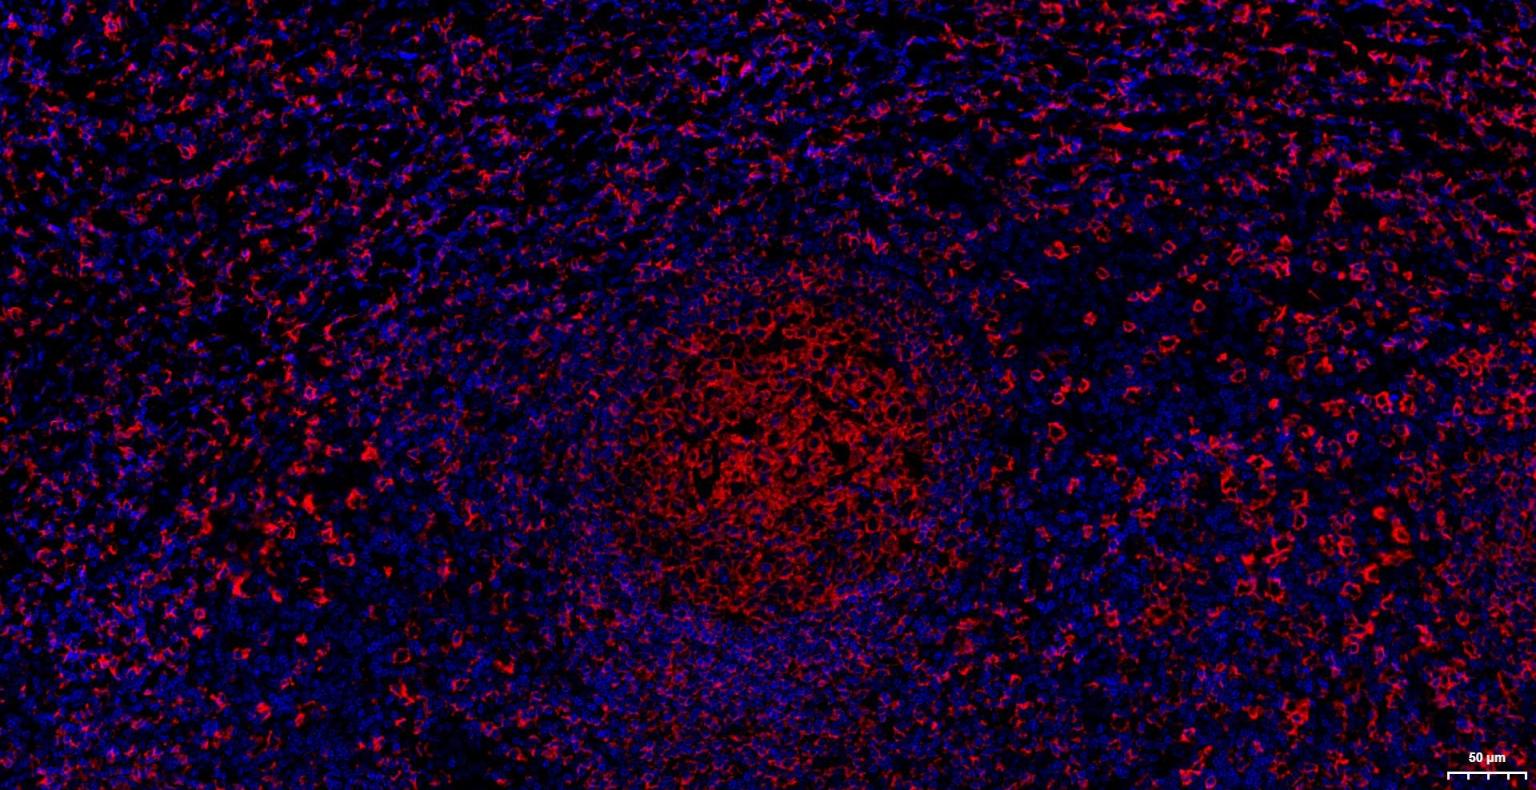

IHC-PHuman1:100-500

IHC-FHuman1:100-500

IFHuman1:100-500